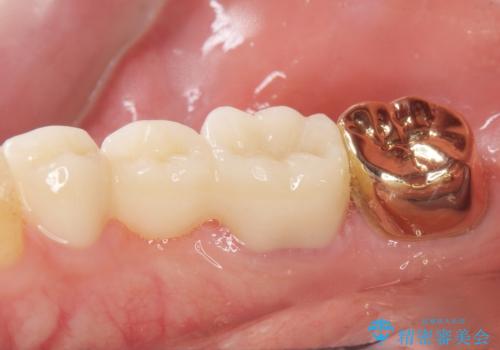

その後ブリッジの治療も希望され、オールセラミックのブリッジによる補綴を行いました。

ゴールド(PGA)クラウンの自然な咬み心地とブリッジの審美的な仕上がりに喜んで頂けました。

右下⑥5④ブリッジ:オールセラミッククラウン スタンダード